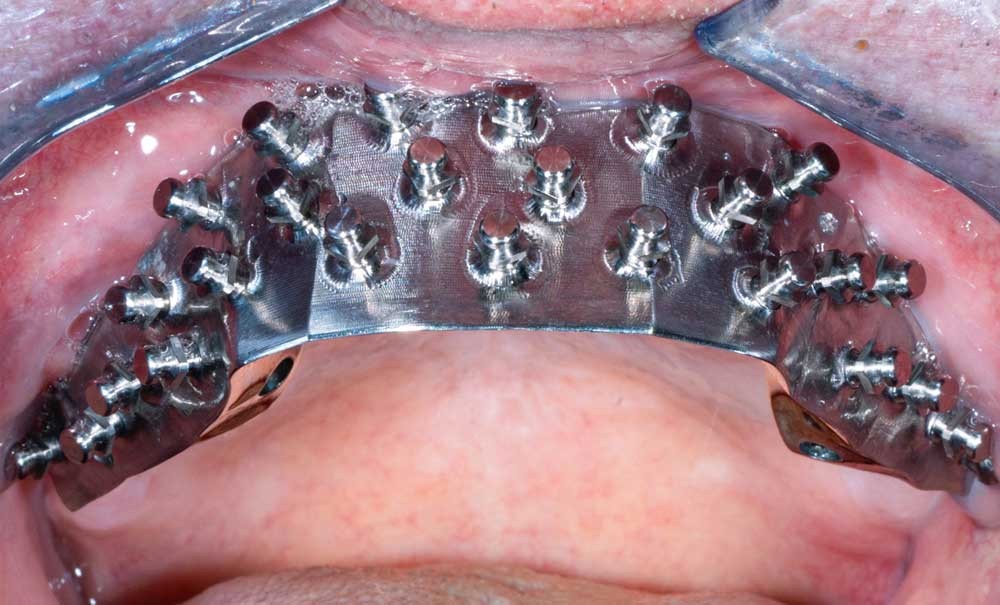

Dans le cas clinique présenté dans cet article, le patient édenté total bimaxillaire se plaint d’une gêne importante et d’une insatisfaction de son sourire en lien avec un plan d’occlusion prothétique inadapté (fig. 1 et 2).

La détermination d’un positionnement correct du maxillaire dans le massif cranio-facial est essentielle lors d’une réhabilitation prothétique étendue. Plans et lignes de références permettent de transférer la position du maxillaire sur articulateur et d’évaluer l’agencement dentaire avec l’harmonie globale du visage [1]. La conception et la réalisation d’une prothèse complète, amovible ou transvissée, sont des exercices difficiles pour le praticien, comme pour le prothésiste de laboratoire, qui doivent imaginer et recréer de manière optimale les fonctions et l’esthétique perdues [2].